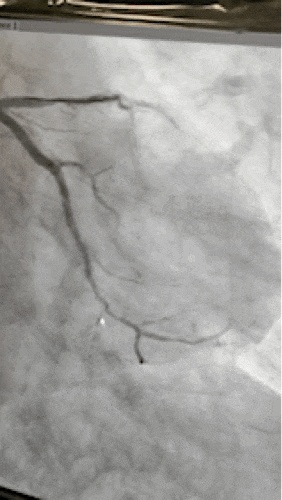

术中王新云团队在血管内超声引导下,在选择微导管及强支撑力导管支持下,使用多种不同硬度及特性的钢丝反复调整方向尝试,最终通过闭塞段至右冠状动脉远端,同样使用了边支球囊锚定技术使预扩张球囊通过硬度很高的钙化病变处,并扩张再通闭塞多年的冠脉... ...成功在右冠植入支架3枚, 8月份,患者再次入院,同样成功完成了左冠回旋支支架内闭塞再通手术。

开通了9年前就闭塞的右冠脉